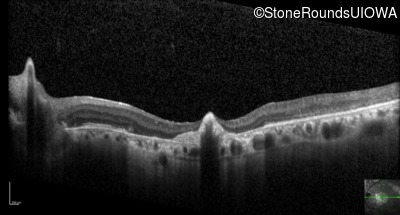

Optical Coherence Tomography - Right - 20/125 -2

Exemplar / OCT Stack

OCT Stack